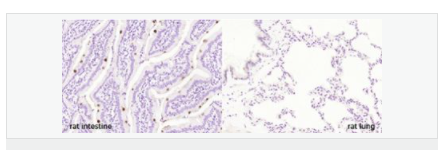

| 產品應用 | ELISA=1:5000-10000 IHC-P=1:100-500 IHC-F=1:100-500 IF=1:100-500 (石蠟切片需做抗原修復) not yet tested in other applications. optimal dilutions/concentrations should be determined by the end user. |

| 產品介紹 | Fc (Ig constant fragment) receptors ensure protection of the host against foreign antigens, such as microorganisms and pathogens, by removing Ig-coated antigen complexes from circulation. Fc receptors are present on lymphoid and myeloid derivatives, where they mediate endocytosis of Ig-antigen complexes, antibody production in B cells through T cell antigen presentation, cytotoxicity and the release of cytokines and reactive oxygen species. The Fc γ-binding protein (FCGBP) interacts with the Fc portion of IgG and MUC2 to mediate the maintenance of the mucosal structure. FCGBP is a 5,405 amino acid protein that contains twelve TIL (trypsin inhibitory-like) domains and thirteen VWFD domains. It is predominantly expressed in placenta and colon epithelium as well as in thyroid and serum. Patients with various autoimmune diseases seemingly have higher levels of FCGBP protein present in their serum. Function: May be involved in the maintenance of the mucosal structure as a gel-like component of the mucosa. Subunit: Interacts with the Fc portion of IgG and with MUC2. Subcellular Location: Secreted. Tissue Specificity: Mainly expressed in placenta and colon epithelium. Expressed in thyroid, and down-regulated in thyroid carcinomas. Present in serum, with higher levels in patients with various autoimmune diseases (at protein level). Similarity: Contains 12 TIL (trypsin inhibitory-like) domains. Contains 13 VWFD domains. SWISS: Q9Y6R7 Gene ID: 8857 Database links: Entrez Gene: 8857 Human SwissProt: Q9Y6R7 Human Unigene: 111732 Human Important Note: This product as supplied is intended for research use only, not for use in human, therapeutic or diagnostic applications. |